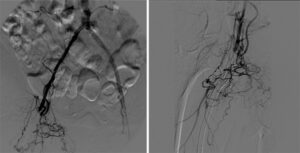

Figure 4. Follow-up angiogram at 40 months (new stent shown with white arrows; occluded stent with black arrows)

Angiography performed 3 years and 8 months following the procedure demonstrated excellent patency of the DBS (Picture). Interventions were performed at sites other than the double-barrel stent.

A Sept. 2016 US follow-up showed continued patency. The patient had no clinical symptoms of claudication.